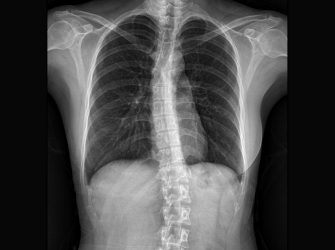

성장판 활성도 및 호르몬 검사 등의 기능적인 검사부터 체형과 측만증, 휜 다리 등의 구조적인 검사까지 놓치지 않으니까

척추 측만증 검사

자세분석검사